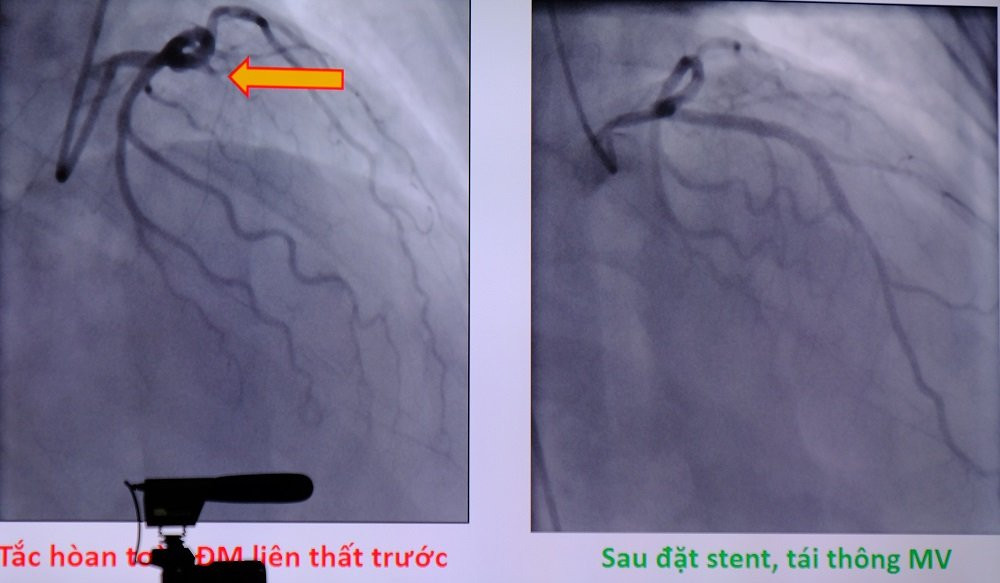

Hình ảnh mạch vành được tái thông sau khi đặt stent.

“Thời gian cửa – bóng (tức là thời gian đến cửa bệnh viện đến khi bóng được nâng lên tái thông dòng máu) trong can thiệp mạch vành cấp cứu rất quan trọng. Trường hợp này đến bệnh viện trong vòng 77 phút (thời gian tiêu chuẩn chung để cứu sống bệnh nhân là dưới 90 phút), khi tiếp nhận thì động mạch nuôi 60% khối lượng cơ tim đã tắc hoàn toàn. Chúng tôi tiến hành đặt stent tái thông mạch vành nhưng bệnh nhân còn sốc tim, tình trạng rất nặng. Ekip điều trị quyết định đặt thêm bóng đối xung động mạch chủ để hỗ trợ sức co bóp cho tim”, bác sĩ Anh kể lại.